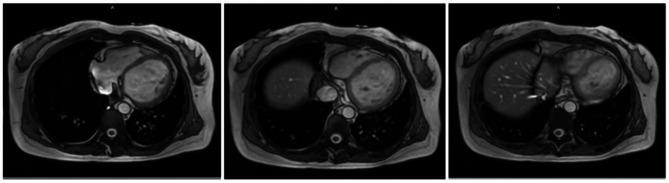

CASE PRESENTATION

In this article, we report a case of a 32-year-old female patient diagnosed with dilated cardiomyopathy. EM was strongly suspected based on a progressive increase in eosinophil count, the absence of known allergens or common etiological factors, elevated eosinophil levels in alveolar lavage fluid, and a diagnosis of eosinophilic pneumonia. However, endocardial myocardial biopsy results failed to show definite evidence of myocarditis. Despite the implementation of various therapeutic interventions including pharmacological treatments, electrical defibrillation, endotracheal intubation, and ventilator-assisted breathing, the patient's condition showed minimal improvement. Subsequent initiation of extracorporeal membrane oxygenation and intra-aortic balloon pump support also failed to achieve the anticipated recovery. The patient subsequently underwent heart transplantation, and cardiac tissue samples were sent for pathology examination. The diagnostic report revealed a large number of eosinophils, confirming the diagnosis of EM. After heart transplantation, the patient's vital signs gradually stabilized, and she was discharged in good condition.

CONCLUSIONS

Endocardial myocardial biopsy plays an important role in diagnosing EM but may yield false-negative results. In this case, heart transplantation provided critical diagnostic information, with the pathology report confirming the presence of eosinophils and supporting the diagnosis of EM.